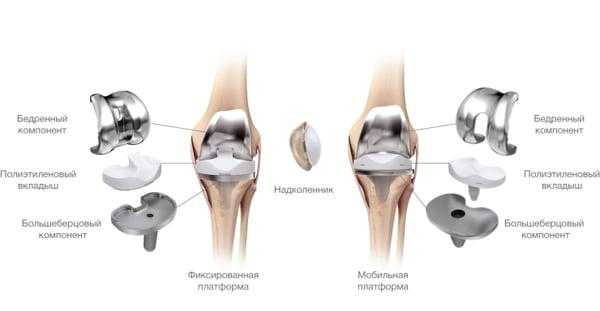

Какие бывают эндопротезы?

Протезные системы бывают с подвижной или неподвижной платформой, а также предусматривающие сохранение или удаление задней крестообразной связки. Различаются по виду фиксации, она может быть цементной, бесцементной и комбинированной.

- Подвижные и неподвижные платформы. Большинству пациентов ставят имплантат с амортизирующим вкладышем, который плотно связан с большеберцовым элементом, то есть изделия с неподвижной платформой. Наличие же мобильного вкладыша внутри металлического большеберцового компонента требует хорошего состояния мышечной системы и капсульно-связочного аппарата, в противном случае может произойти смещение протеза.

Имплантант позволяет осуществлять движения в двух плоскостях.